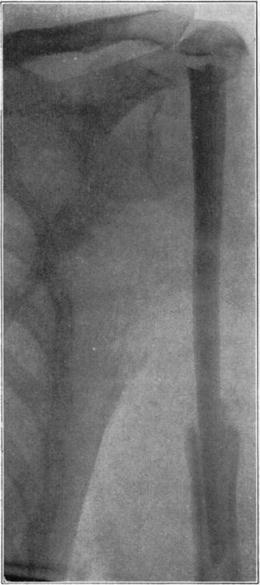

Case 4. Large splinter (a) displaced into soft parts from fresh fracture of tibia.

Case 4. The same (a) seven years later, showing reduction in size of splinter and apparent replacement by very spongy new bone.